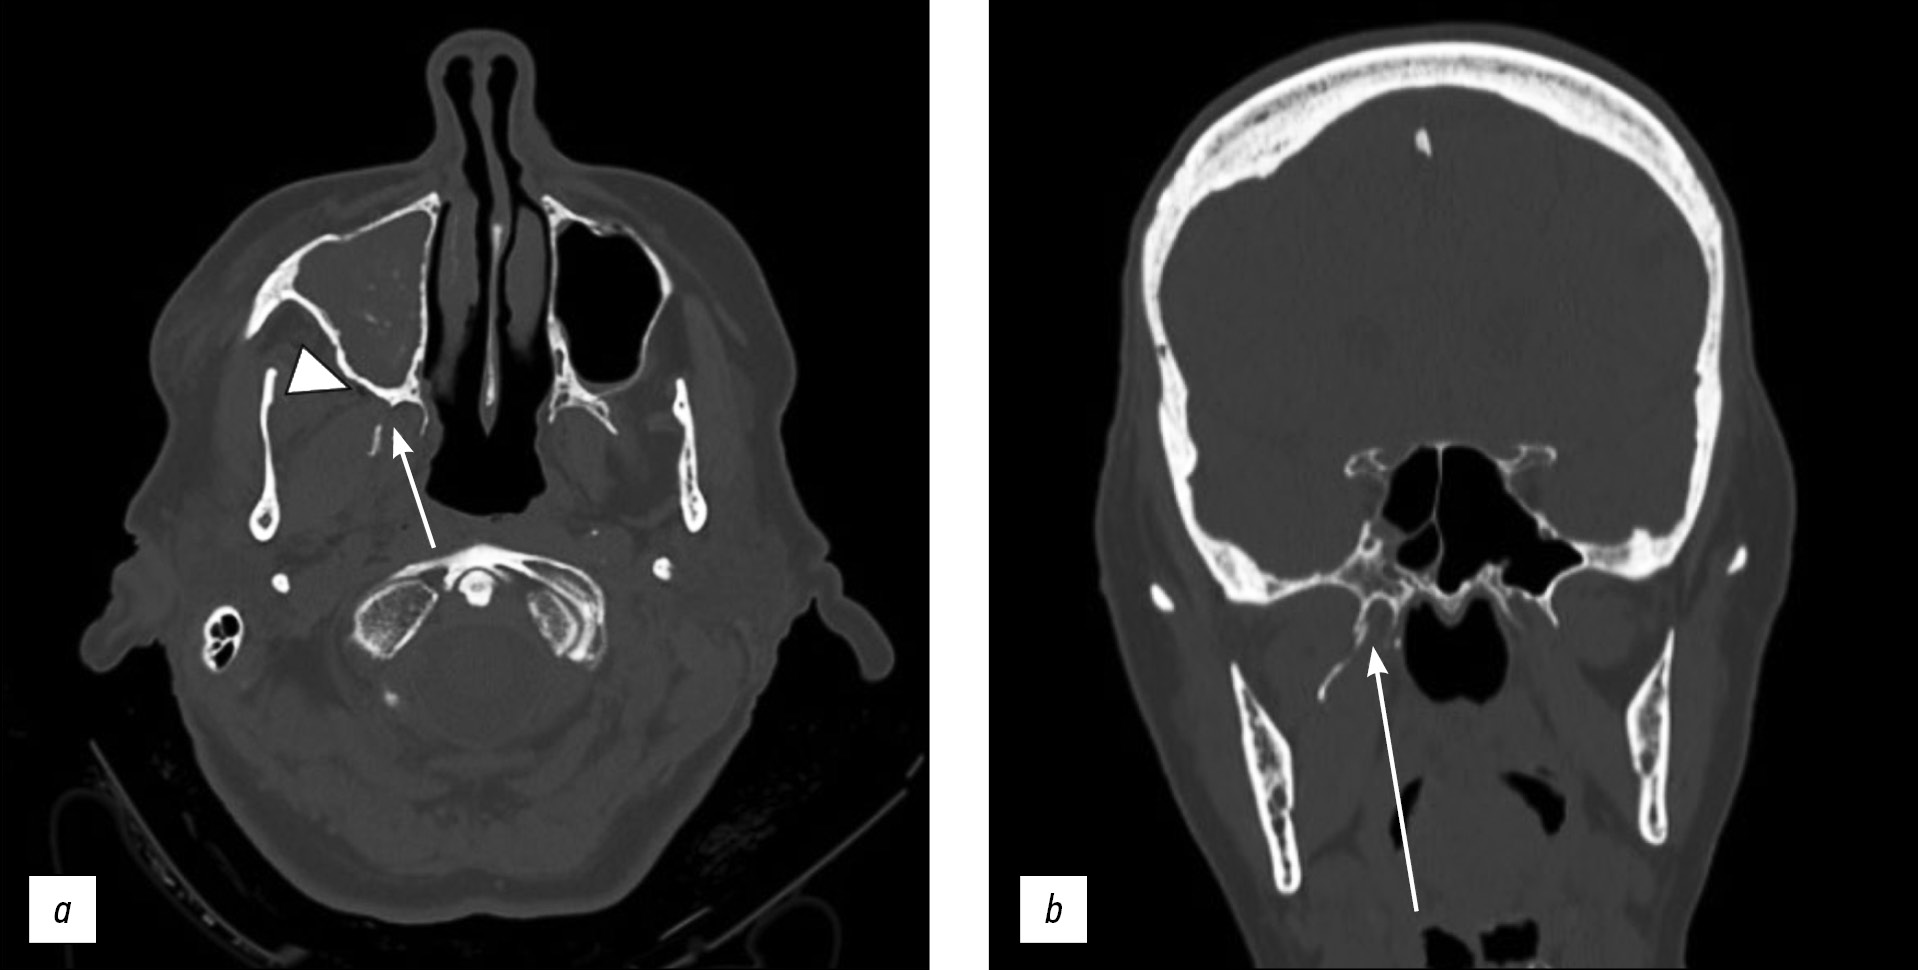

计算机断层扫描显示右侧翼突板单侧骨折,同侧咀嚼上颌间隙有肺气肿迹象。此外,该患者还发现了右侧上颌窦侧壁骨折,有血窦征象。未检测到颅底骨折或硬脑膜损伤。患者接受了保守治疗。